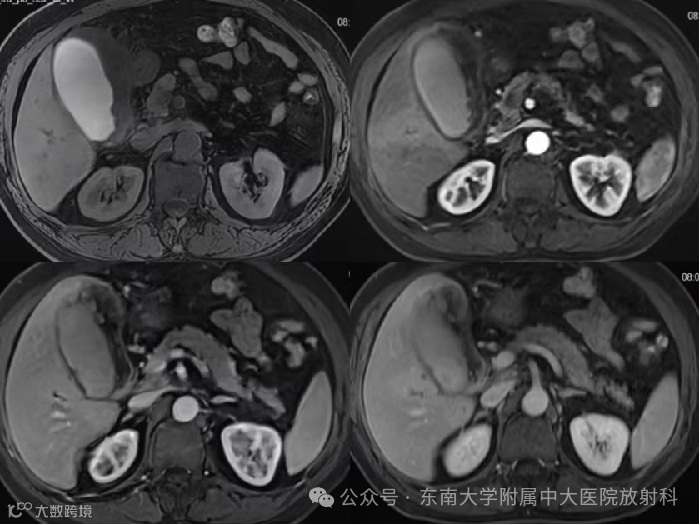

男,67岁 -

主诉:上腹部绞痛半月余 -

现病史:患者半个月前出现上腹部绞痛,夜间加剧,不伴发热,无寒战,无恶心呕吐,无腹泻,无反酸嗳气,无胸闷气喘,无呼吸困难,无黄疸 -

影像学表现